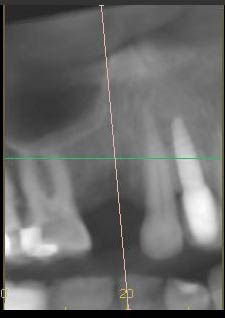

Radiographic situation.

Pre-operative CT.